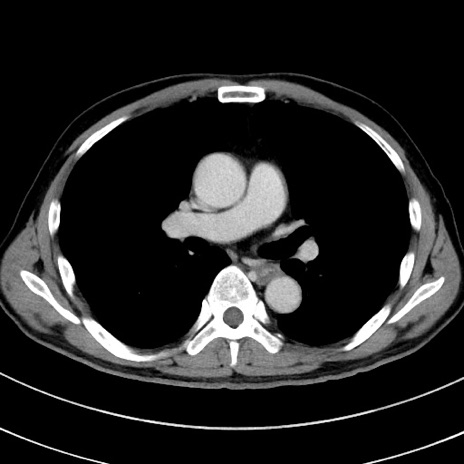

症例8(横断像)

【症例】 60歳代男性

【主訴】 黒色吐物

【現病歴】 4日前から嘔気自覚、2日前の朝食後にも嘔気あり、自分で手で嘔吐反射起こし嘔吐したところ血が混ざっていたため受診。

【既往歴】 5年前汎発性腹膜炎を伴う急性虫垂炎で手術、高血圧、前立腺肥大症、高脂血症

【身体所見】 腹部正中に手術癩痕あり 腹部平坦・軟圧痛なし膨満感あり

【データ】WBC 8400、CRP 4.54